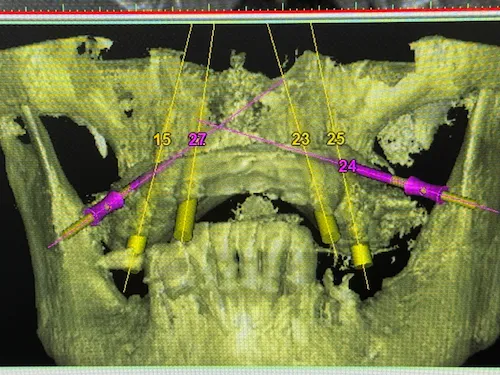

Bevor an einen operativen Eingriff gedacht werden kann, stehen als erstes Röntgenbilder mithilfe der Digitalen Volumentomographie auf dem Programm. Hier sind die Überreste in Ober-und Unterkiefer gut zu sehen, vor allem aber die Positionen der abgebrochenen Zahnwurzeln. Auf Basis der Bilder können die Positionen für die insgesamt 8 Implantate auf den Millimeter genau geplant werden: Unser Patient wird jeweils 4 Implantate im Ober-und Unterkiefer erhalten, die im Nachgang jeweils mit einem festsitzenden Zahnersatz versorgt werden. Die Einheilphase dauert zwischen 4 und 6 Monate, prognostiziert Dr. Mintert, der Spezialist für Implantate in der ZPK Herne.

Implantatplanung - Oberkiefer - All-on-Four Konzept

Implantatplanung - Unterkiefer - All-on-Four Konzept

Unter Einsatz der SIMPLANT® Planungssoftware kann der Implantolgoe die optimalen Implantatpositionen vorab am Computer planen, wobei sämtliche Planungsdaten anschließend in die Herstellung einer individuellen Bohrschablone einfließen. Die Bohrschablone ermöglicht ein punktgenaues, schonendes Einsetzen der Implantate an den zuvor geplanten Positionen, minimiert das Verletzungsrisiko und beschleunigt letztendlich die Heilung.

Das Behandlung mit Camfour™ sieht 4-6 Implantate je Zahnbogen vor. Meist reichen jedoch 4 Implantate aus. Die speziell für diesen Zweck ausgelegten Zahnimplantate werden mit einem Winkel von bis zu 45° in den Knochen eingebracht. Durch die geneigten Implantate ist der Spezialist für Implantologie unabhängiger vom noch vorhandenen Knochenvolumen und kann ohne einen vorherigen Knochenaufbau implantieren. Wichtig ist, dass die Zahnimplantate bereit unmittelbar nach Einsetzen stabil im Kieferknochen sitzen. Dies wird durch das spezielle All-on-4 ® / All-on-6 ®- Implantationsverfahren sichergestellt. Eine hohe „Primärstabilität“ der Implantate ist die wichtigste Grundvoraussetzung für eine Sofortversorgung mit Zahnersatz noch am gleichen Tag.